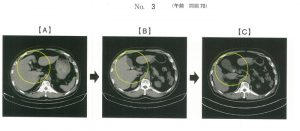

問題70

腹部CTを以下に示す。胆石が半年間で胆嚢内をAからCまで移動した。

Cの状態を表すのはどれか。

1.嵌頓

2.侵入

3.転位

4.停留

5.迷入